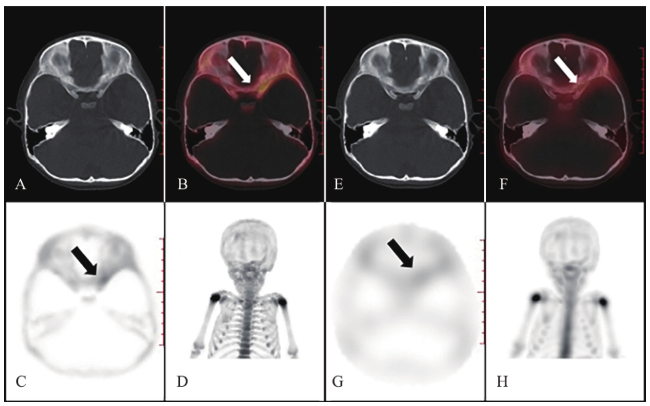

SPECT/CT断层融合显像核医学医师的诊断信心评分为3(2~4)分,xSPECT/CT为5(2~5)分,xSPECT/CT断层融合显像可提高核医学医师对患儿骨转移瘤的诊断信心(Z = -6.501,P < 0.001)。1例骨转移瘤患儿的xSPECT/CT与SPECT/CT系列图像比较见图1

图1 一例骨转移瘤患儿xSPECT/CT与SPECT/CT系列图像的比较

注:A~D为xSPECT/CT系列图像,A为CT图像,B为xSPECT/CT图像,C为xSPECT图像,D为xSPECT局部最大密度投影(MIP)图像;E~H为SPECT/CT系列图像,E为CT图像,F为SPECT/CT图像,G为SPECT图像,H为SPECT局部MIP图像。箭头所指最后被证实为骨转移病灶。xSPECT/CT图像质量相对较好,可清晰显示患儿左侧蝶骨局部放射性浓聚灶,而SPECT/CT图像质量相对差,在相同部位未见明确异常放射性浓聚。2名核医学医师对该例进行诊断时,在xSPECT/CT断层融合显像下,均明确患儿存在骨转移,诊断信心评分为4分;在SPECT/CT断层融合显像时,因未见明确放射性浓聚而漏诊,诊断信心评分为2分。